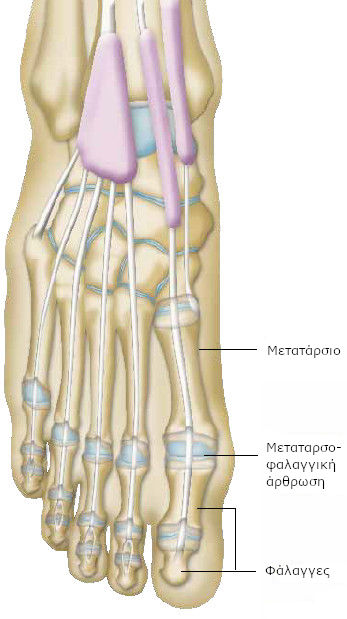

Όλα τα δάκτυλα του άκρου ποδός αποτελούνται από δύο ή τρία μικρότερα οστά (τις φάλαγγες των δακτύλων).

Στη βάση των δακτύλων, η πρώτη φάλαγγα συνδέεται με ένα μακρύτερο οστό (το μετατάρσιο), με μια άρθρωση που ονομάζεται μεταταρσοφαλαγγική άρθρωση.

Τα οστά συνδέονται με τους μυς με προσφύσεις, τους τένοντες, χάρη στους οποίους οι δάκτυλοι μπορούν να λυγίζουν και να τεντώνονται.